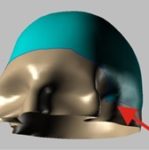

3D model

Protože poškození bylo velmi vážné, rozhodl se výrobce vyrobit protézu ze dvou částí.

Dr. P. Kasprzak vysvětluje – největší protéza zaznamenaná v literatuře měla 400 cm2. V našem případě – 280 cm2. Jedná se o druhý největší případ na světě (samozřejmě ze známých případů).